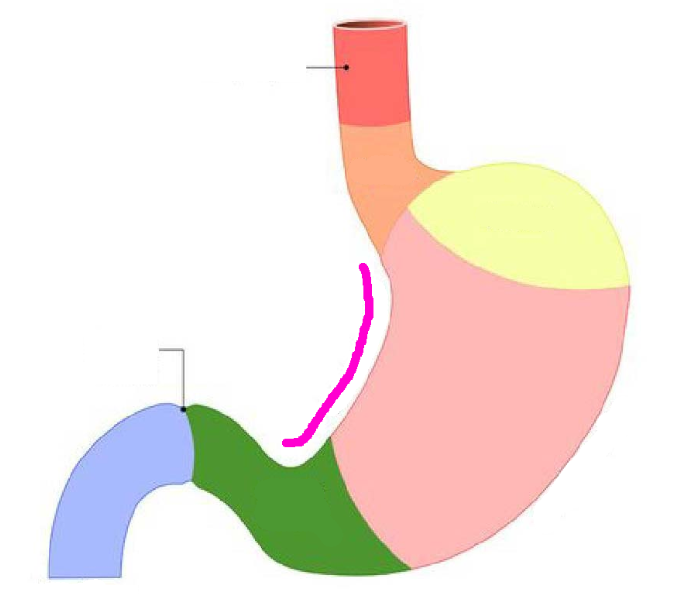

Esophagus

Diaphragm

Greater curvature of stomach

pink line

Lesser curvature of stomach

pink line

Fundus region

purple highlight

Cardia region

green highlight

Body of stomach

blue highlight

Pylorus of stomach

yellow + orange highlights

Cardiac orifice

Esophageal lumen

Pyloric sphincter

Pyloric orifice

Duodenum

blue highlight